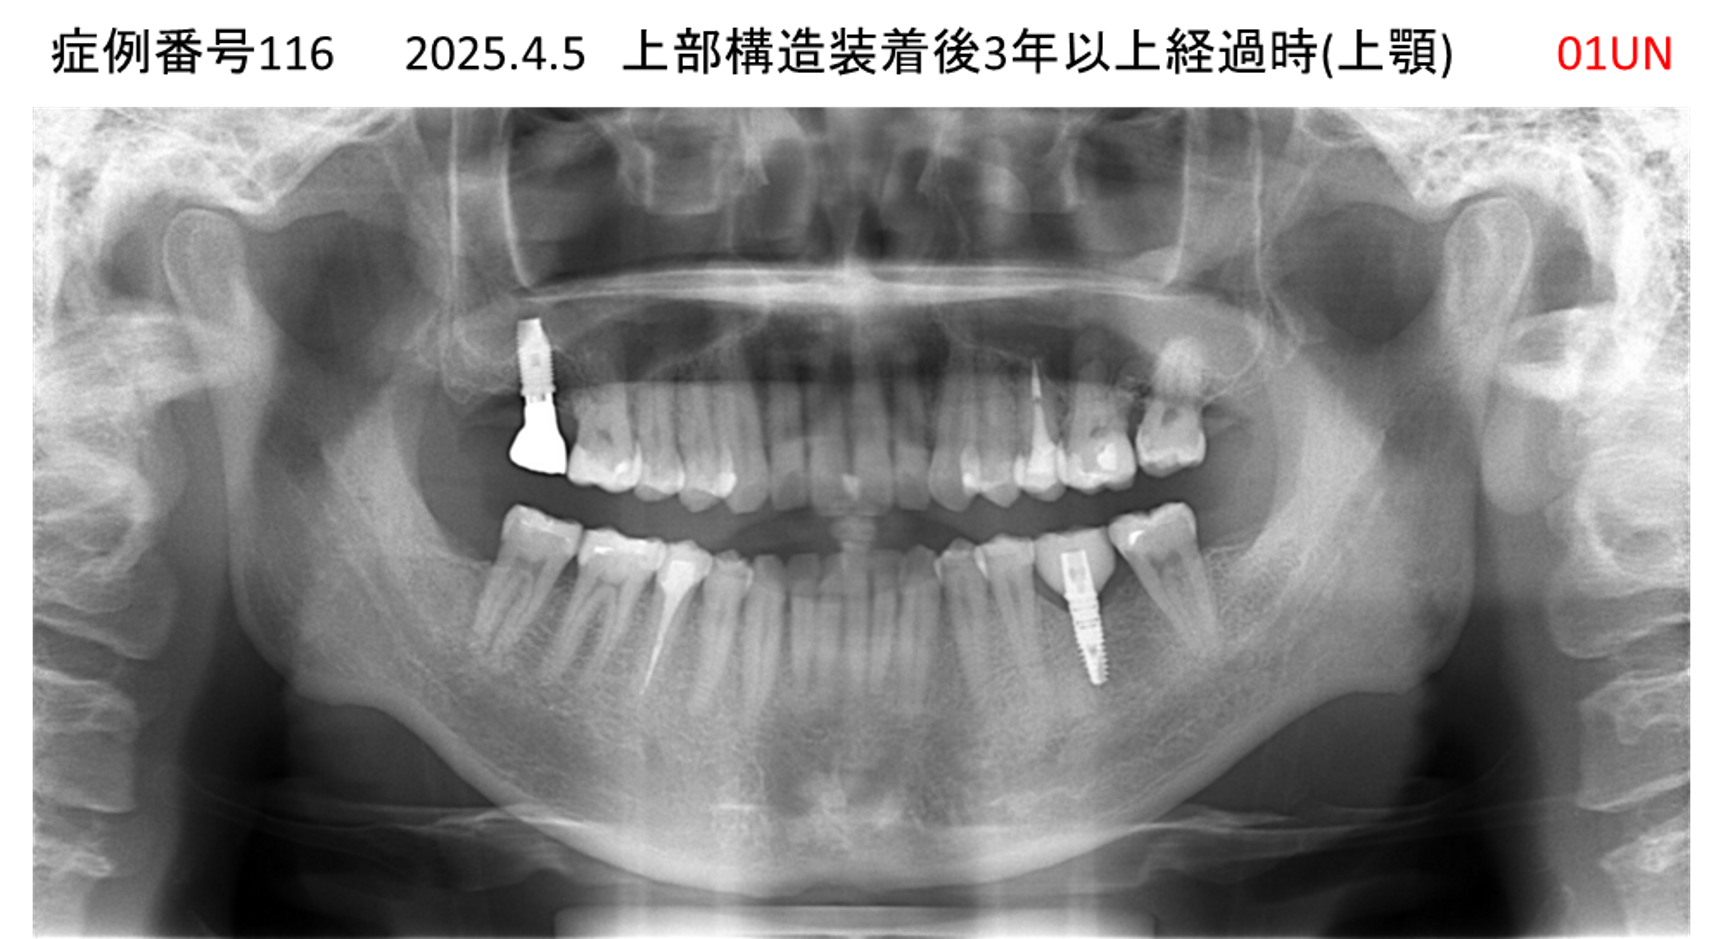

奥歯で噛めない患者様のインプラント症例

| 治療名称 |

インプラント |

| 治療費用 |

365万円+税 |

| 治療期間 |

5か月 |

| 患者さんの症状(主訴) |

奥歯で噛めない。上の前歯が揺れてきた。 |

| 治療内容 |

抜歯即時インプラント |

| 治療結果 |

食事に困らない。見た目がとても良くなった。 |

| 治療の注意点(リスク/副作用) |

インプラントが壊れたら再治療が必要 |